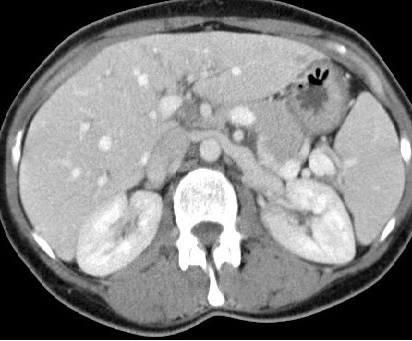

下列静脉造影的影像提示盆腔充血综合症(Presence of one or more of the following Venographic appearances suggests PCS)【1】

1. 卵巢静脉扩张>6mm (Dilation of the ovarian vein (diameter >6 mm))

2. 卵巢静脉返流(Ovarian vein reflux)

3. 子宫静脉充盈(Uterine vein engorgement)

4. 卵巢静脉丛充血(Congestion of the ovarian venous plexus)

5. 盆腔静脉跨越中线充盈 (Filling of pelvic veins across midline)

6. 会阴及股内侧静脉曲张(Filling of vulvovaginal or thigh varicosities)